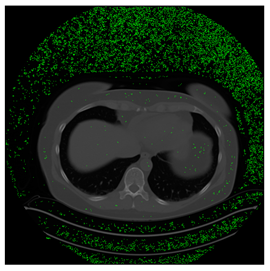

Breast-MRI-NACT-Pilot is an MRI-type image database, collecting breast medical images of 64 patients. Some samples are shown in Figure 12a.

Figure 12.

Sampled images in the tested benchmark databases: (a) Breast-MRI-NACT-Pilot (breast), (b) ACRIN-DSC-MR-Brain (brain), (c) NIH (chest), (d) Lung-PET-CT-Dx (lung), (e) Prostate-MRI (prostate), and (f) Other grayscale standard images.

ANIH is an X-ray type image database collecting chest medical images. Some samples are shown in Figure 12c.

Lung-PET-CT-Dx is a CT-type image database collecting lung medical images. Some samples are shown in Figure 12d.

In this subsection, we describe three experiments used to measure the performance of the proposed method. The first experiment shows the stegoimage and marks the pixels’ positions that have been modified during the embedding process, as shown in Table 2, Table 3, Table 4, Table 5, Table 6 and Table 7. To make modified pixel positions have a pronounced effect, we set bpp (bit per pixel) rate at 0.05 and 0.025. It can be seen from the results that the proposed local complexity function can distinguish ROI and RONI from most of the medical images, so modified pixels are mainly gathered in RONI. However, it is observed that the proposed local complexity function cannot distinguish between ROI and RONI in the Prostate-MRI database due to the relative complexity of the image. Besides, “Modified BPP” represents the proportion of pixels in the image that have been modified. We observed that the performance of “baboon” in the grayscale standard images database is poor because that image’s pixels are relatively complex. It becomes challenging to select the more embeddable pixels based on the proposed local complexity function. Nevertheless, the modified pixel positions in other grayscale standard images, such as Lena and Barbara, are relatively smooth, verifying that our local complexity function is also applicable to general images.